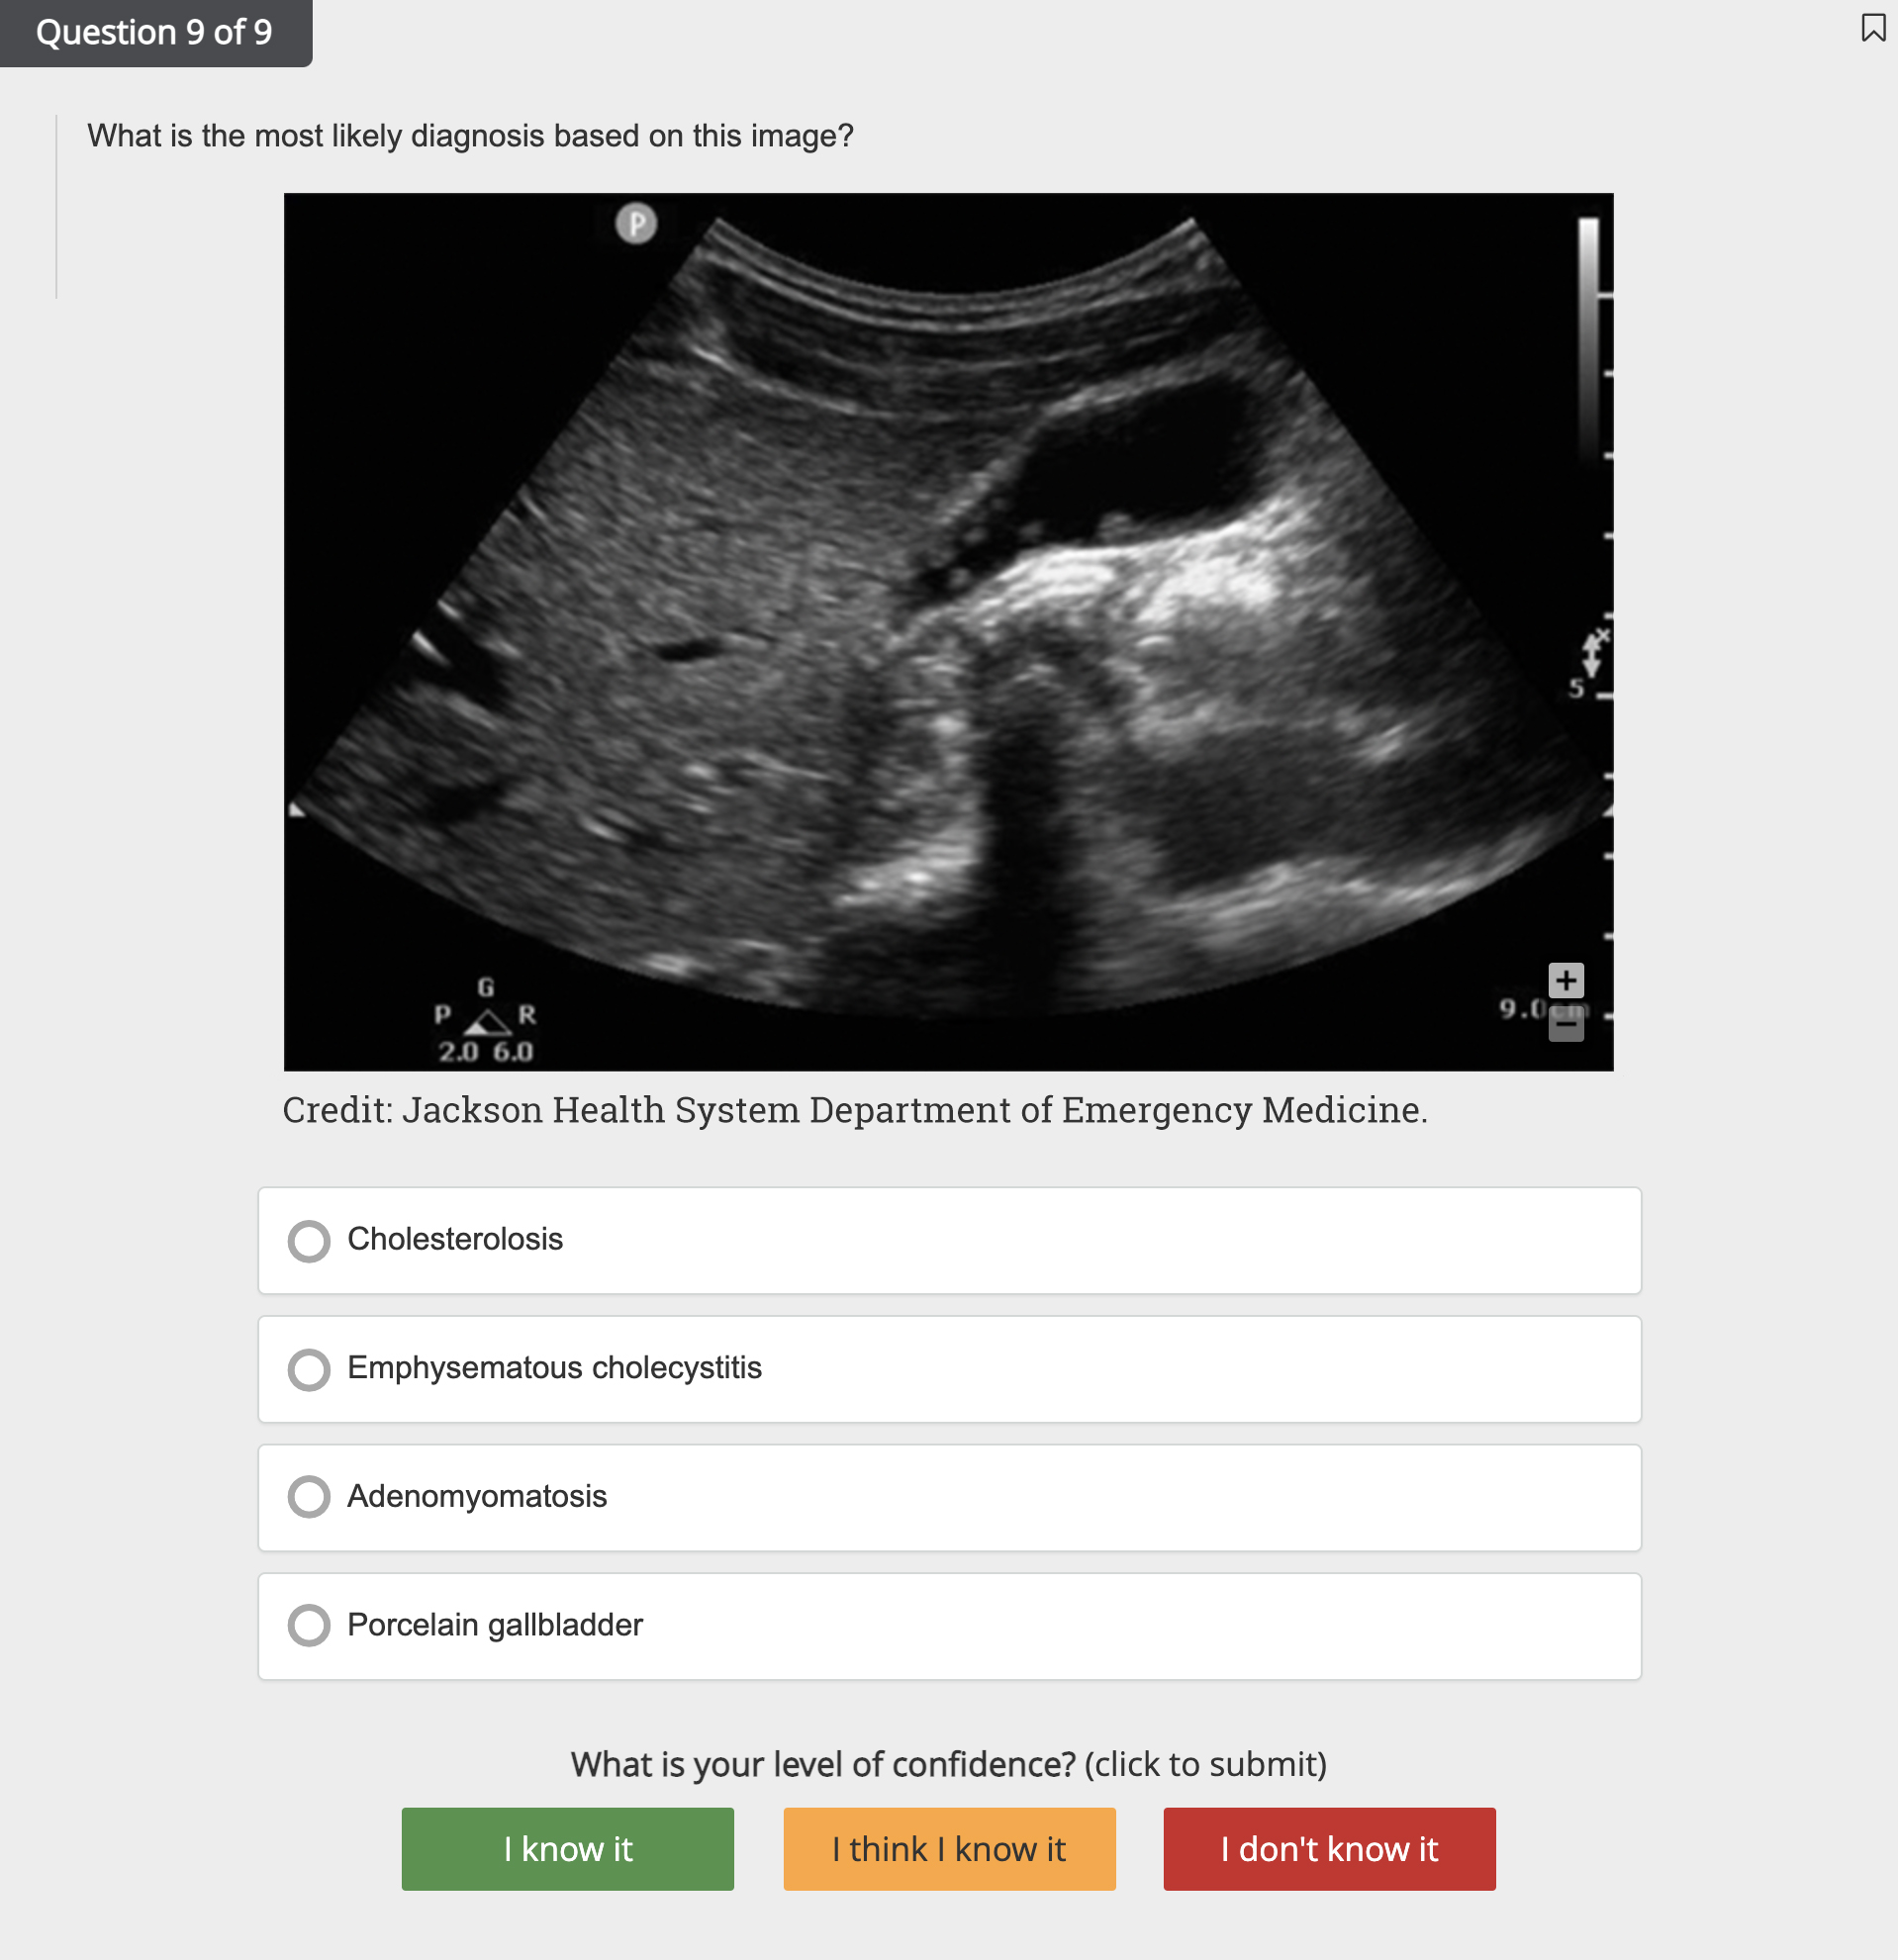

- Review numerous image- and video-based ultrasounds, along with quick study aid infographics

- Study relevant imagery and videos in tandem with answer explanations

- Explore the First Aid Kit library with 550+ ultrasound images, infographics, and videos